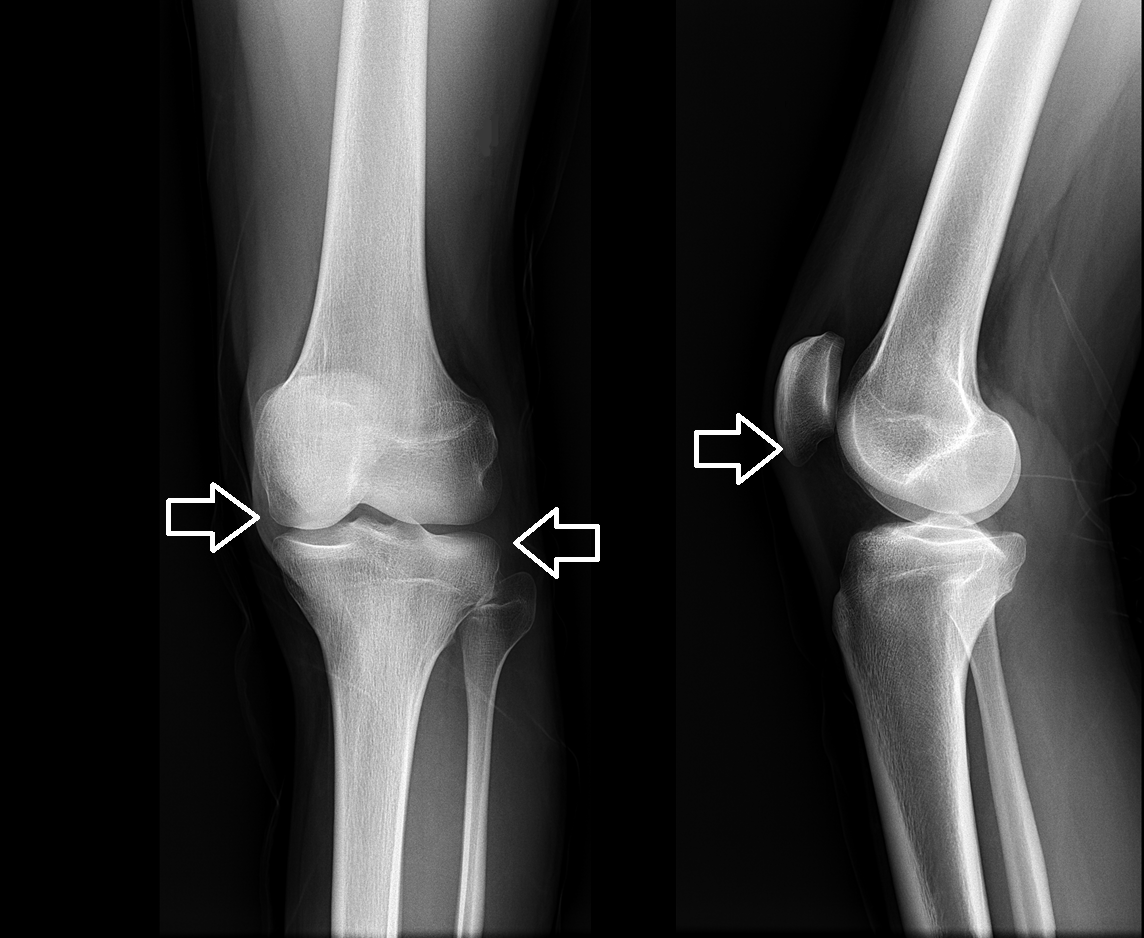

W końcu zostałam zbadany przez lekarza. Była starszy i myślałam, że na pewno ma doświadczenie. Przynajmniej taką miałam nadzieję... Bez zbędnych ceregieli zrobił mi pełne badanie, które obejmowało prześwietlenia rentgenowskie oraz badania krwi i moczu.

Na kolejnej wizycie dosłownie w ciągu kilku minut zdiagnozował u mnie wtórną chorobę zwyrodnieniową stawów z powikłaniami . Szczerze mówiąc, nie bardzo rozumiałam, co mówił. Wyjaśnił mi coś w niejasny sposób i odesłał do domu z listą tabletek.

Ale największą rzeczą, która mnie zszokowała, była przyczyna mojego bólu. „ To kwestia wieku ” – wyjaśnił mi lekarz. Ale w jakim wieku! Mam dopiero 53 lata i czuję się aktywną, pełną energii mamą moich 18-16-letnich dzieci, a nie starszą panią cierpiącą na chorobę zwyrodnieniową stawów.

Dzień 35: Miałam badania i prześwietlenia rentgenowskie. Żadnych objawów choroby zwyrodnieniowej stawów! Chrząstka w moich stawach była jak u 20-letniej dziewczyny. Lekarz stwierdził, że prawdopodobnie na poprzednim zdjęciu RTG wystąpiła wada, dlatego diagnoza choroby zwyrodnieniowej stawów była błędna.